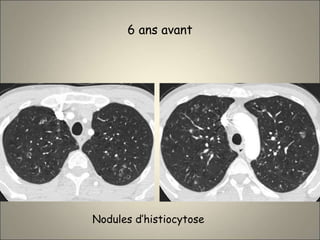

Patient de 32 ans tabagique

6 ans avant

Nodules d’histiocytose